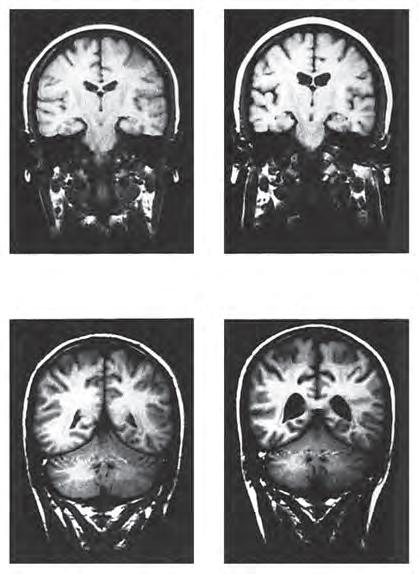

Figura 16.7 Geni identici, destini diversi. Sebbene i due membri di ciascuna coppia di gemelli monozigoti qui mostrati abbiano gli stessi geni, solo uno dei gemelli (quello con i ventricoli più dilatati) ha sviluppato la schizofrenia. [Fonte: E.F. Torrey et al., 1994. Schizophrenia and manic depressive disorder. Basic Books: New York; RMI per gentile concessione di E. Fuller Torrey and Daniel Weinburger.]

be causare l’allargamento ventricolare nei pazienti con schizofrenia. In effetti, tra gemelli che sono discordanti per la schizofrenia, l’ippocampo e l’amigdala sono più piccoli nel gemello malato. Gli studi post-mortem sui pazienti schizofrenici hanno rivelato anomalie in molte parti del sistema limbico, inclusi l’ippocampo, l’amigdala e le regioni paraippocampali. Le cellule piramidali ippocampali delle persone con schizofrenia appaiono in numero minore e disorganizzate (Figura 16.9), probabilmente a causa di una disposizione sinaptica anomala sia degli ingressi sia delle uscite di queste cellule (F. Chen et al., 2020; Heckers e Konradi, 2002). Le evidenze suggeriscono che possano esserci anomalie diffuse nell’attività del sistema limbico che si estendono dall’ippocampo fino ad altre strutture limbiche, quali la corteccia entorinale, la corteccia paraippocampale e la corteccia cingolata, così come una connettività tra l’ippocampo e altre regioni corticali (Avery et al., 2018; Bubb et al., 2018).